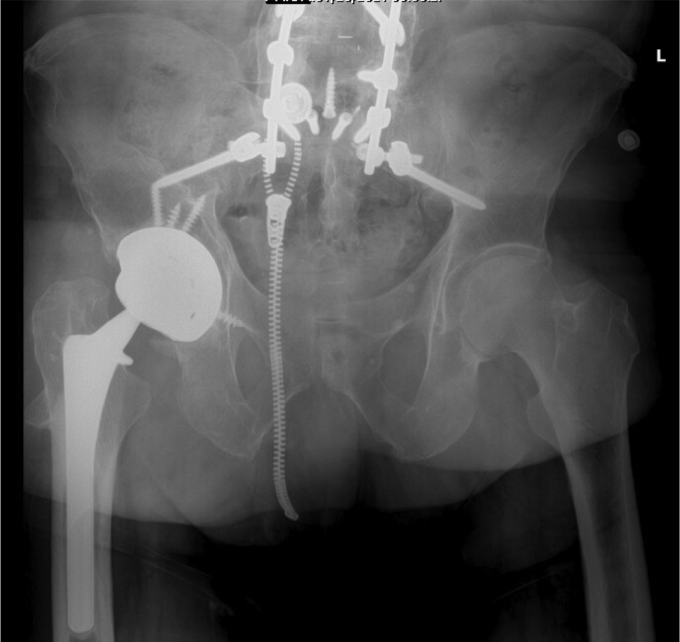

The patient’s postoperative course was uneventful. He was made 50% weight-bearing with no active abduction immediately after the surgery. He was discharged home on postoperative day 3 and instructed to take oral antibiotics for 2 weeks. Six weeks after the surgery, he was progressed to full weight-bearing, and all precautions were released. At his latest follow-up visit, at 6 months postoperatively, he was doing well without any further complication. Postoperative imaging illustrated well-fixed components without signs of loosening (Fig. 6). He reported 8/10 satisfaction with his surgery, and his UCLA Activity Score was- regularly participates in mild activities. His Harris Hip Score improved from 45 preoperatively to 67 after surgery.

Figure 6.

Six-month postoperative AP pelvis illustrating stable components without loosening or other complication.